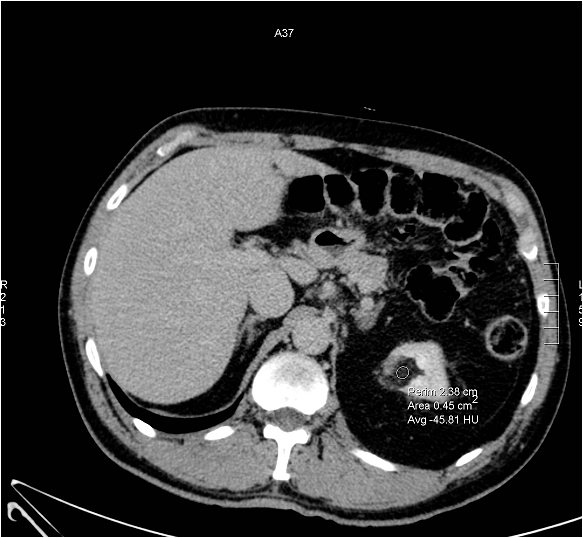

Image

Figure 4. Angiomyolipoma (well circumscribed hyperechoic mass) US image

On the CT scan the fat content is highlighted as a typically hypodense area, where negative HU values can be detected.

Figure 5. Hypodense (fat containing) well circumscribed mass: CT morphology is consistent with angiomyolipoma.